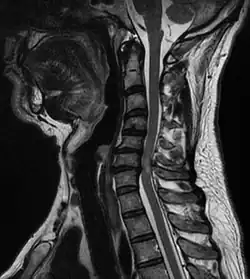

![]() Tumor causando compresión de la médula espinal | ||

La compresión medular o compresión de la médula espinales una forma de mielopatía en la que la médula espinal está comprimida. Las causas pueden ser debidas a fragmentos óseos de una fractura vertebral, un tumor, abscesos, rotura de disco intervertebral u otra lesión.[1]

El diagnóstico se realiza mediante radiografías pero preferiblemente resonancia magnética (RMN) de toda la columna vertebral.[4][5]